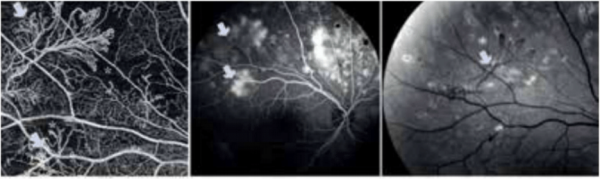

OCT Angio: בדיקת הדמיה חדשה, לא פולשנית, שנכנסה לשימוש בשנת 2016 ונמצאת עדיין רק בחלק מהמרכזים בעולם אם כי חלקה באבחון עולה בהתמדה. בישראל היא כבר מופעלת במספר מרכזים. הבדיקה מזהה באמצעות קרן אור (בדומה ל-OCT) תזוזת כדוריות דם ולכן יכולה להדגים זרימת דם, נוכחות כלי דם תקינים או חולים, כלי דם חדשים וכן אזורים בהם יש חסימות כלי דם. בחלק מהמקרים ממצאי הבדיקה דומים לממצאים שמתקבלים בבדיקת ה-FA, אך ללא הצורך בהזרקת חומר ניגוד. חידוש זה משמעותי בעיקר לאנשים הרגישים לחומר הניגוד. בנוסף, עם הפעלתה, ניתן לחסוך בצורך בנוכחות רופא בעת ההדמיה, דבר העשוי להקל מאוד על העומס ולייצר זמינות טובה יותר של הבדיקות[3][4][5]. ההדמיה מסוגלת להבחין בין שכבות הרשתית השונות ולמפות את אזורי הפתולוגיה בצורה שלא באה לידי ביטוי בשום הדמיה הקיימת.

הטיפול בנוגדי VEGF השונים ניתן בהזרקה תוך עינית בלבד. ההזרקה נעשית בתנאים סטריליים, לאחר הרדמה מקומית ואינה דורשת אשפוז. בעקבות הזריקה חלה בחלק ניכר מהמקרים הפחתה בדלף מכלי הדם, נסיגת בצקת, ירידה משמעותית בעובי הרשתית (מודגם בבדיקה OCT) נסיגת כלי דם חדשים ושיפור בראייה. בדרך כלל יש צורך בהזרקות חוזרות. ההזרקות ניתנות אחת לחודש עד להשגת התוצאה הרצויה ולאחר נכן במרווחים עולים, לפעמים עד להפסקתם (תמונות 1–3).